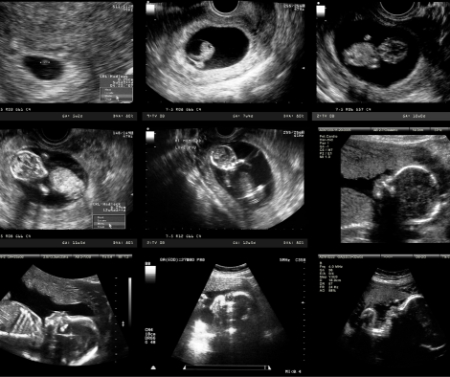

سونوگرافی (Ultrasound) یکی از پرکاربردترین و مطمئنترین روشها برای بررسی سلامت مادر و جنین در دوران بارداری است. این روش بدون درد، غیرتهاجمی و کاملاً ایمن بوده و امکان مشاهدهی رشد جنین، وضعیت جفت و مایع آمنیوتیک، و تشخیص ناهنجاریهای احتمالی را فراهم میکند.

آشنایی با زمان مناسب انجام سونوگرافیها، انواع آنها و نحوهی تفسیر نتایج، به والدین کمک میکند تا با آرامش و اطمینان دوران بارداری را سپری کنند.

انواع سونوگرافی در دوران بارداری

۱. سونوگرافی اولیه (هفته ۶ تا ۹)

این سونوگرافی معمولاً اولین تصویربرداری از جنین است.

هدف: تایید وجود بارداری، تعیین تعداد جنینها و بررسی محل لانهگزینی (داخل رحم یا خارج از رحم)

مشاهده: قلب جنین در این مرحله قابل تشخیص است و پزشک میتواند ضربان قلب را اندازهگیری کند.

نکته: اگر بارداری چندقلو باشد، در این سونوگرافی مشخص میشود و مراقبتهای ویژه آغاز میگردد.

۲. سونوگرافی NT (Nuchal Translucency) (هفته ۱۱ تا ۱۴)

این سونوگرافی برای تشخیص ریسک اختلالات ژنتیکی انجام میشود.

هدف: اندازهگیری ضخامت پشت گردن جنین برای بررسی احتمال سندرم داون و سایر اختلالات کروموزومی

روش: همراه با آزمایش خون (Double یا Triple Test) دقت تشخیص بالاتر میرود.

نکته: ضخامت بیش از حد پشت گردن، نیاز به بررسیهای تکمیلی دارد، اما همیشه به معنای اختلال نیست.

۳. سونوگرافی آنومالی (هفته ۱۸ تا ۲۲)

مهمترین سونوگرافی دوران بارداری برای ارزیابی ساختار بدن جنین است.

هدف: بررسی کامل اندامها، از جمله قلب، مغز، کلیهها، ستون فقرات و اندام حرکتی

تشخیص: ناهنجاریهای مادرزادی مثل نقصهای قلبی، شکاف کام و اختلالات ستون فقرات

نکته: این سونوگرافی بهترین زمان برای تشخیص مشکلات ساختاری است، زیرا اندامها به اندازه کافی رشد کردهاند.

۴. سونوگرافی رشد و سلامت جنین (سهماهه سوم)

در این مرحله، رشد و وضعیت سلامت جنین به دقت بررسی میشود.

هدف: کنترل وزن، قد و رشد جنین، بررسی میزان مایع آمنیوتیک و جریان خون در جفت و بند ناف

تشخیص: بررسی محدودیت رشد داخل رحمی، مشکلات جفت و نشانههای استرس جنین

نکته: تعداد این سونوگرافیها بسته به وضعیت مادر و جنین متفاوت است و پزشک تصمیم میگیرد.